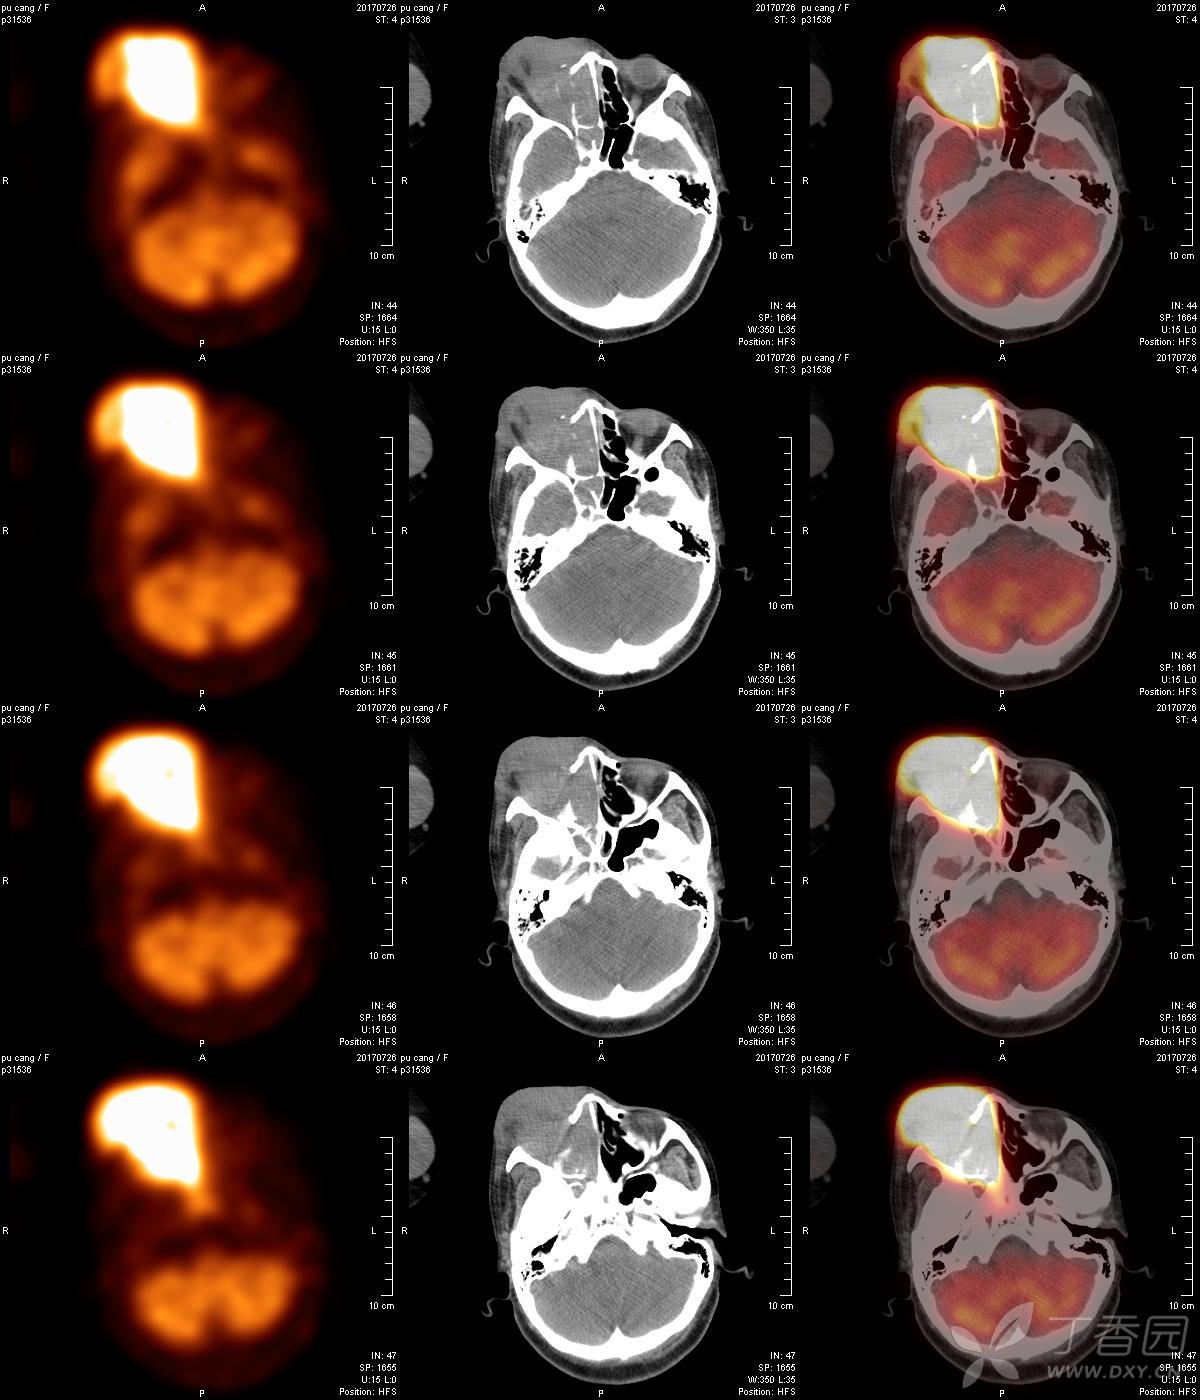

pet-ct:肺病变性质? - 影像医学和核医学讨论版 -丁香园论坛

图片尺寸1200x1400